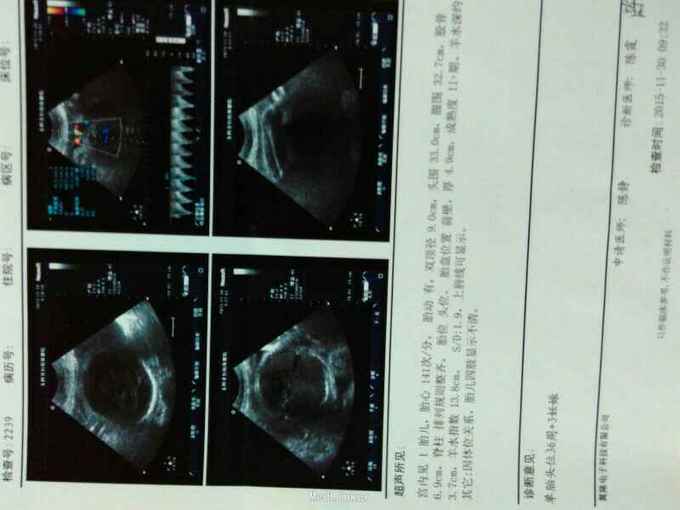

孕妇王某,25岁,因停经39+2周,不规律腹痛1天入院,4年前行剖宫产术。T

T36.5°C BP120/70 mmHg,心肺听诊 无异常,腹彭隆,肝脾肋下未及,下腹见一长约12cm横行瘢痕。 产科检查:宫高:30cm,腹围:103cm,胎位ROA,胎心138次/分,宫口开大2cm,胎膜未破,头先露,S-1.

诊断为39+2周妊娠,G1P1L1A1 ROA 瘢痕子宫 双子宫双阴道。 入院后完善各项检查,因相对性头盆不称,瘢痕子宫 双子宫双阴道行剖宫产术,助娩一男婴,体重3000g,阿氏评分1-5分钟均10分,探查见双子宫,右侧子宫妊娠,于右侧子宫右侧及左侧子宫右侧各探及一输卵管,应家属及产妇要求行双侧输卵管结扎术,术顺,术后补液抗生素治疗。